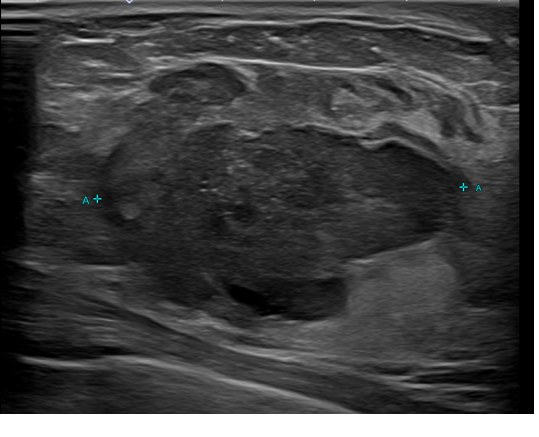

상기환자 외부검사이후 추적검사차 내원하신  30대후반 여성분으로 의심스러운

우측혹 조직검사 시행해 침윤성암으로 진단되었습니다